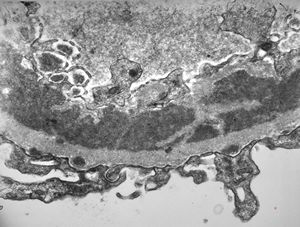

F,14y. | Alport syndrome - split and laminated, thick/thin basement membranes